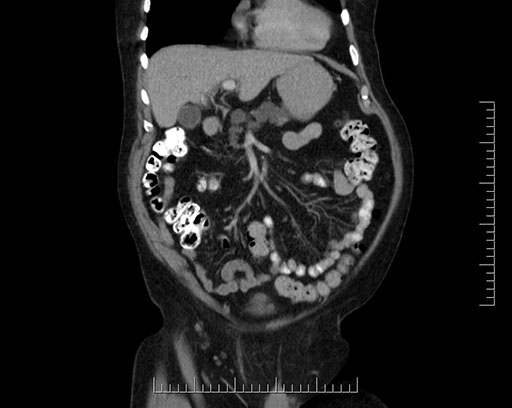

Whipple (pancreaticoduodenectomy) [case 7]

Imaging Analysis

Look through the patient's CT scan to identify any areas of concern for the necessary procedure.

Coronal - stented